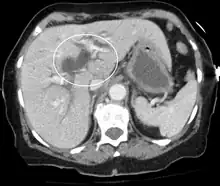

Biliary-tract dilation due to obstruction as seen on CT scan (frontal plane)

Biliary-tract dilation due to obstruction as seen on CT scan (axial plane)

Most people presenting with jaundice have various predictable patterns of liver panel abnormalities, though significant variation does exist. The typical liver panel includes blood levels of enzymes found primarily from the liver, such as the aminotransferases (ALT, AST), and alkaline phosphatase (ALP); bilirubin (which causes the jaundice); and protein levels, specifically, total protein and albumin. Other primary lab tests for liver function include gamma glutamyl transpeptidase (GGT) and prothrombin time (PT).[37] No single test can differentiate between various classifications of jaundice. A combination of liver function tests and other physical examination findings is essential to arrive at a diagnosis.[38]

Medical imaging such as ultrasound, CT scan, and HIDA scan are useful for detecting bile-duct blockage.[41]